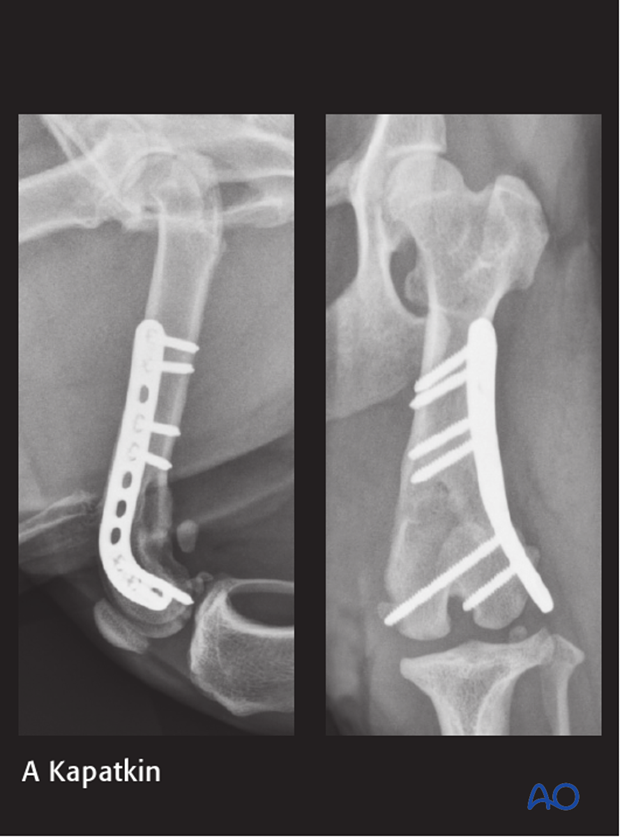

10-year-old MC Jack Russell Terrier of 6 kg.

Stepped on by owner 1 week before presentation.

The fracture was repaired using a 2.0 mm distal femoral plate in bridging fashion.

7-week postoperative radiographs.

The patient reported fully healed at the 12-week postoperative radiographic control.